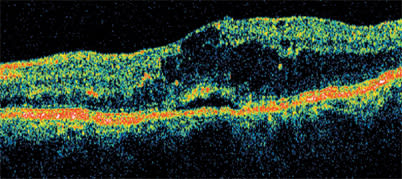

Diabetic macular edema with serous retinal detachment responds very well to treatment with steroids.

Using the Stratus OCT is an excellent way determine that subclinical posterior hyaloid traction is the cause of tractional retinal detachment and diabetic macular edema. Note the tent-like appearance of the tractional retinal detachment. Surgery is the best treatment choice.

The Stratus OCT is also useful for visualizing the several types of retinal detachments associated with DME. Serous detachments, which appear more concave in shape, generally respond well to steroid treatment. However, tractional retinal detachments, which have a tent-like appearance, do not respond to medical therapy. For any improvement to occur, the hyaloid must be surgically removed.